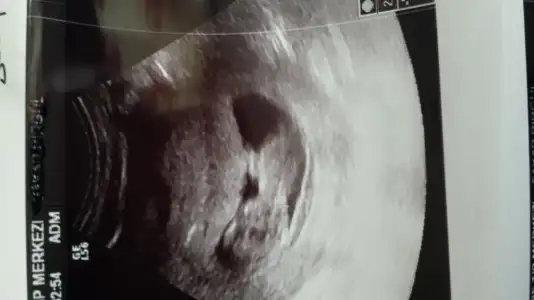

Erkeğe daha çok benzettim ikinci resimden dolayı. Ama kesin diyemem.Kızlar cinsiyet konusunda tahmin alabilirmiyim??Eki Görüntüle 1522208 Eki Görüntüle 1522219

Teşekkür ederim ben yurt dışındayım ama ultrasonda fark olurmu bilmiyorum en belirgin resmi diye koymuştum başka resim yükleyim , yorumun için çok sağol canımErkeğe benziyor ama çok değişik bir ultrason Fotoğrafı.

BANA YORUM YOKMU KIZLAR11 + 0 haftalık bebeğim yorum alabilirmiyiz

Henüz nubu oluşmamış bu teori için 12-13 haftalar en ideal zamanlar.

Bebeginiz erkek bence saglikli bi sekilde kucaginiza alin inss...